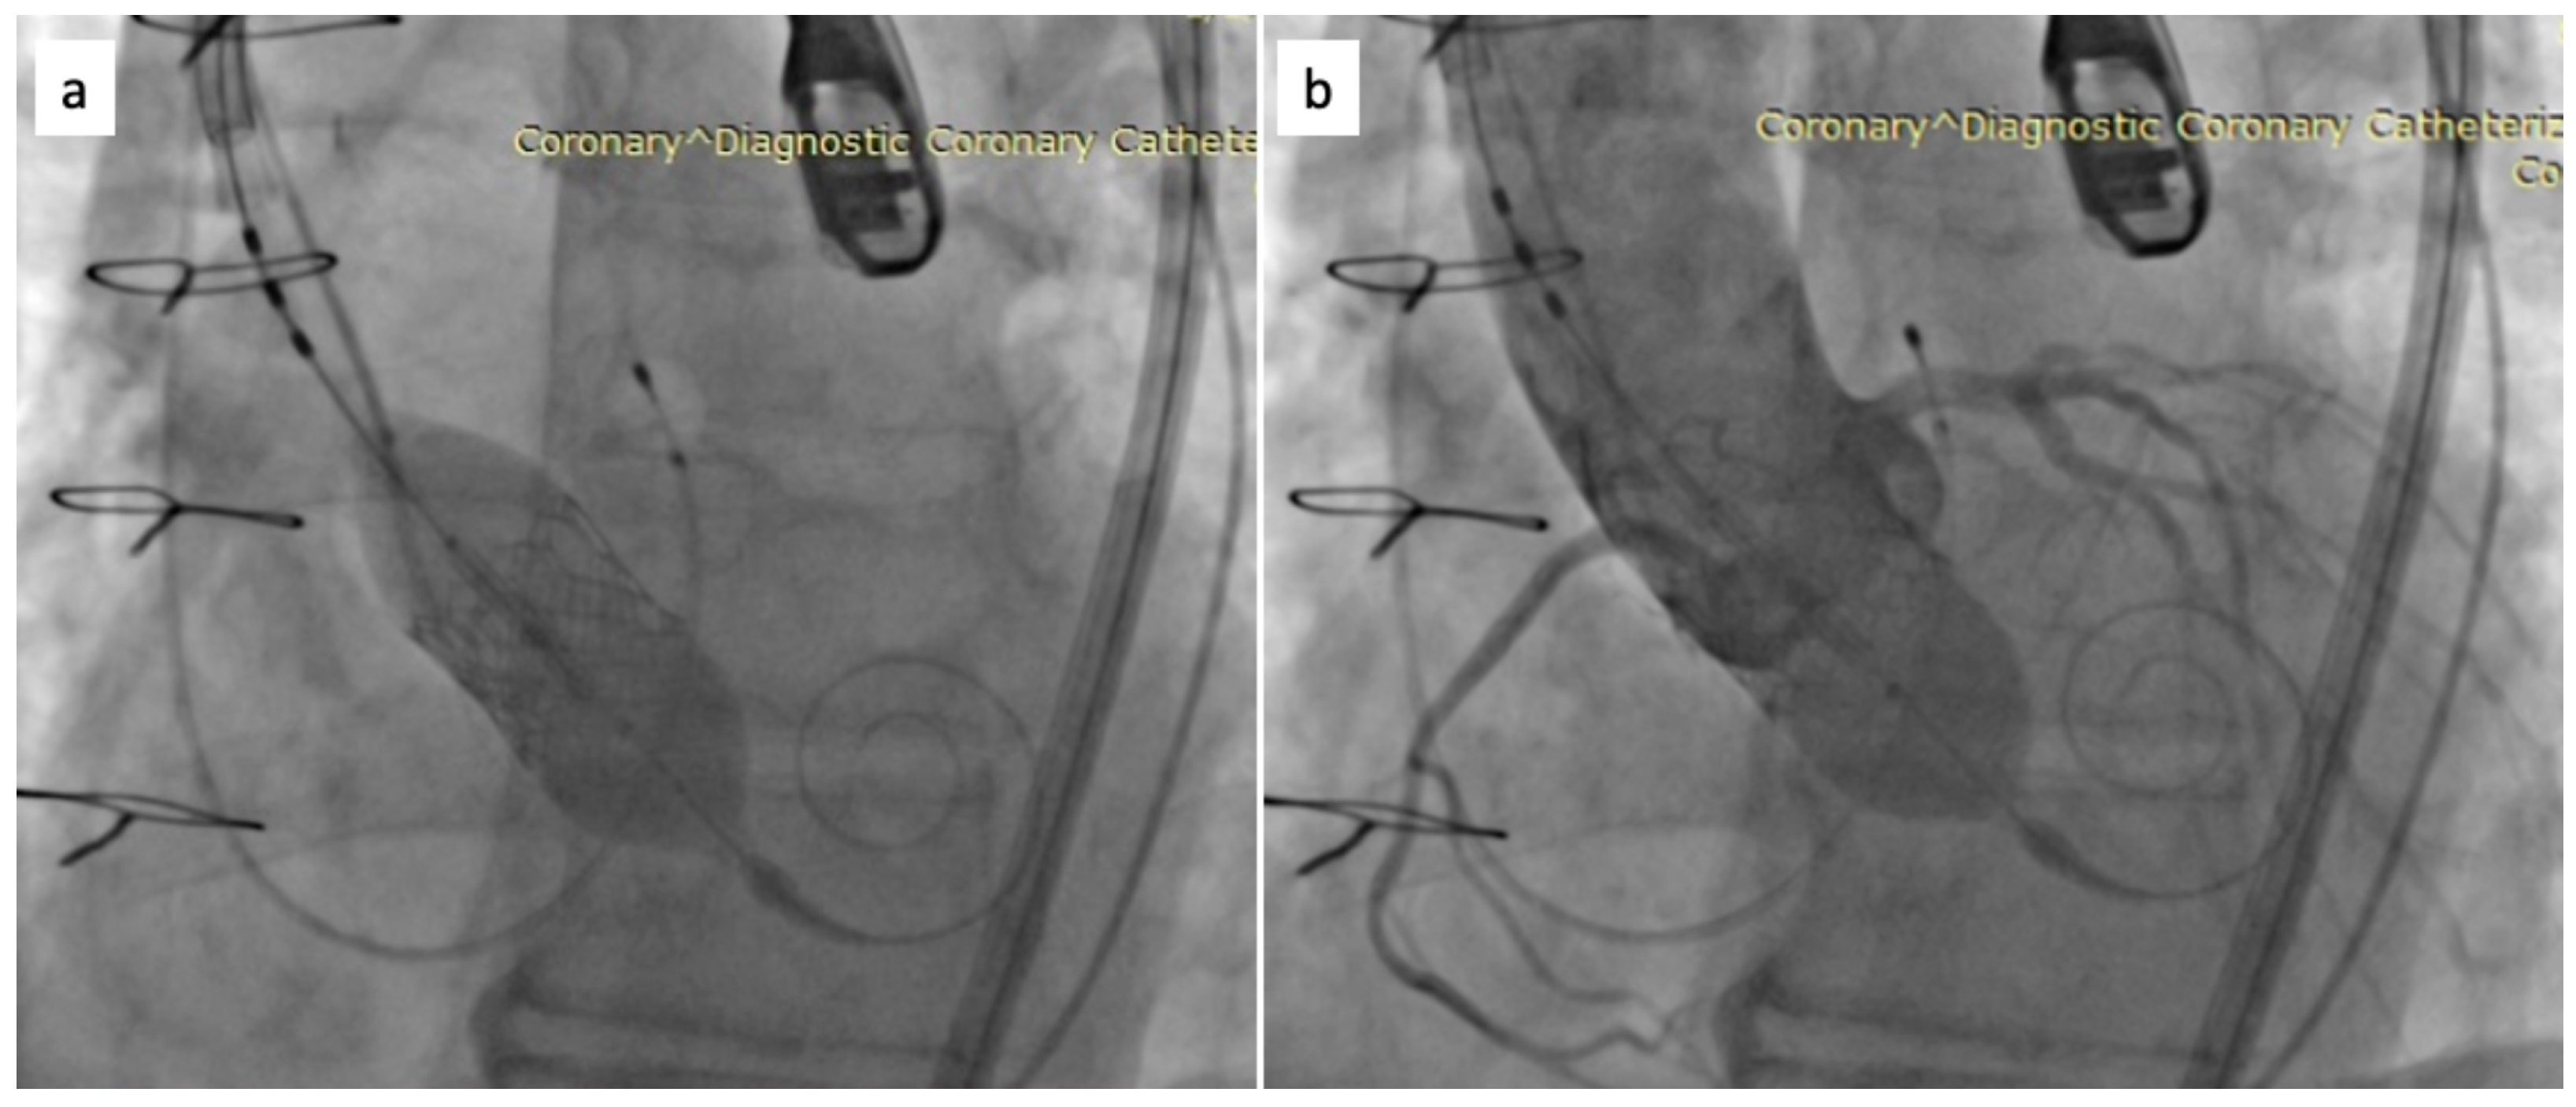

Percutaneous diagnosis was accomplished using a 6 French (F) sheath inserted via the left femoral artery. Subsequently, a Safari stiff guidewire was introduced, followed by the insertion of a specific eSheath through the right femoral artery. The hydrophilic guidewire, along with the AL 1 catheter, was navigated retrogradely across the aortic valve. Following this, the hydrophilic guidewire was exchanged for the stiff Safari guidewire, and the Sapien 3 valve, size 23 mm, was positioned at the level of the aortic annulus. Figure 3 presents a fluoroscopy image showing valve positioning. With the aid of rapid pacing, the valve was expanded (nominal volume +1 mL). During transesophageal echocardiography (TEE) assessment, a paravalvular leak was detected.

Figure 3. Fluoroscopy image—Valve positioning.